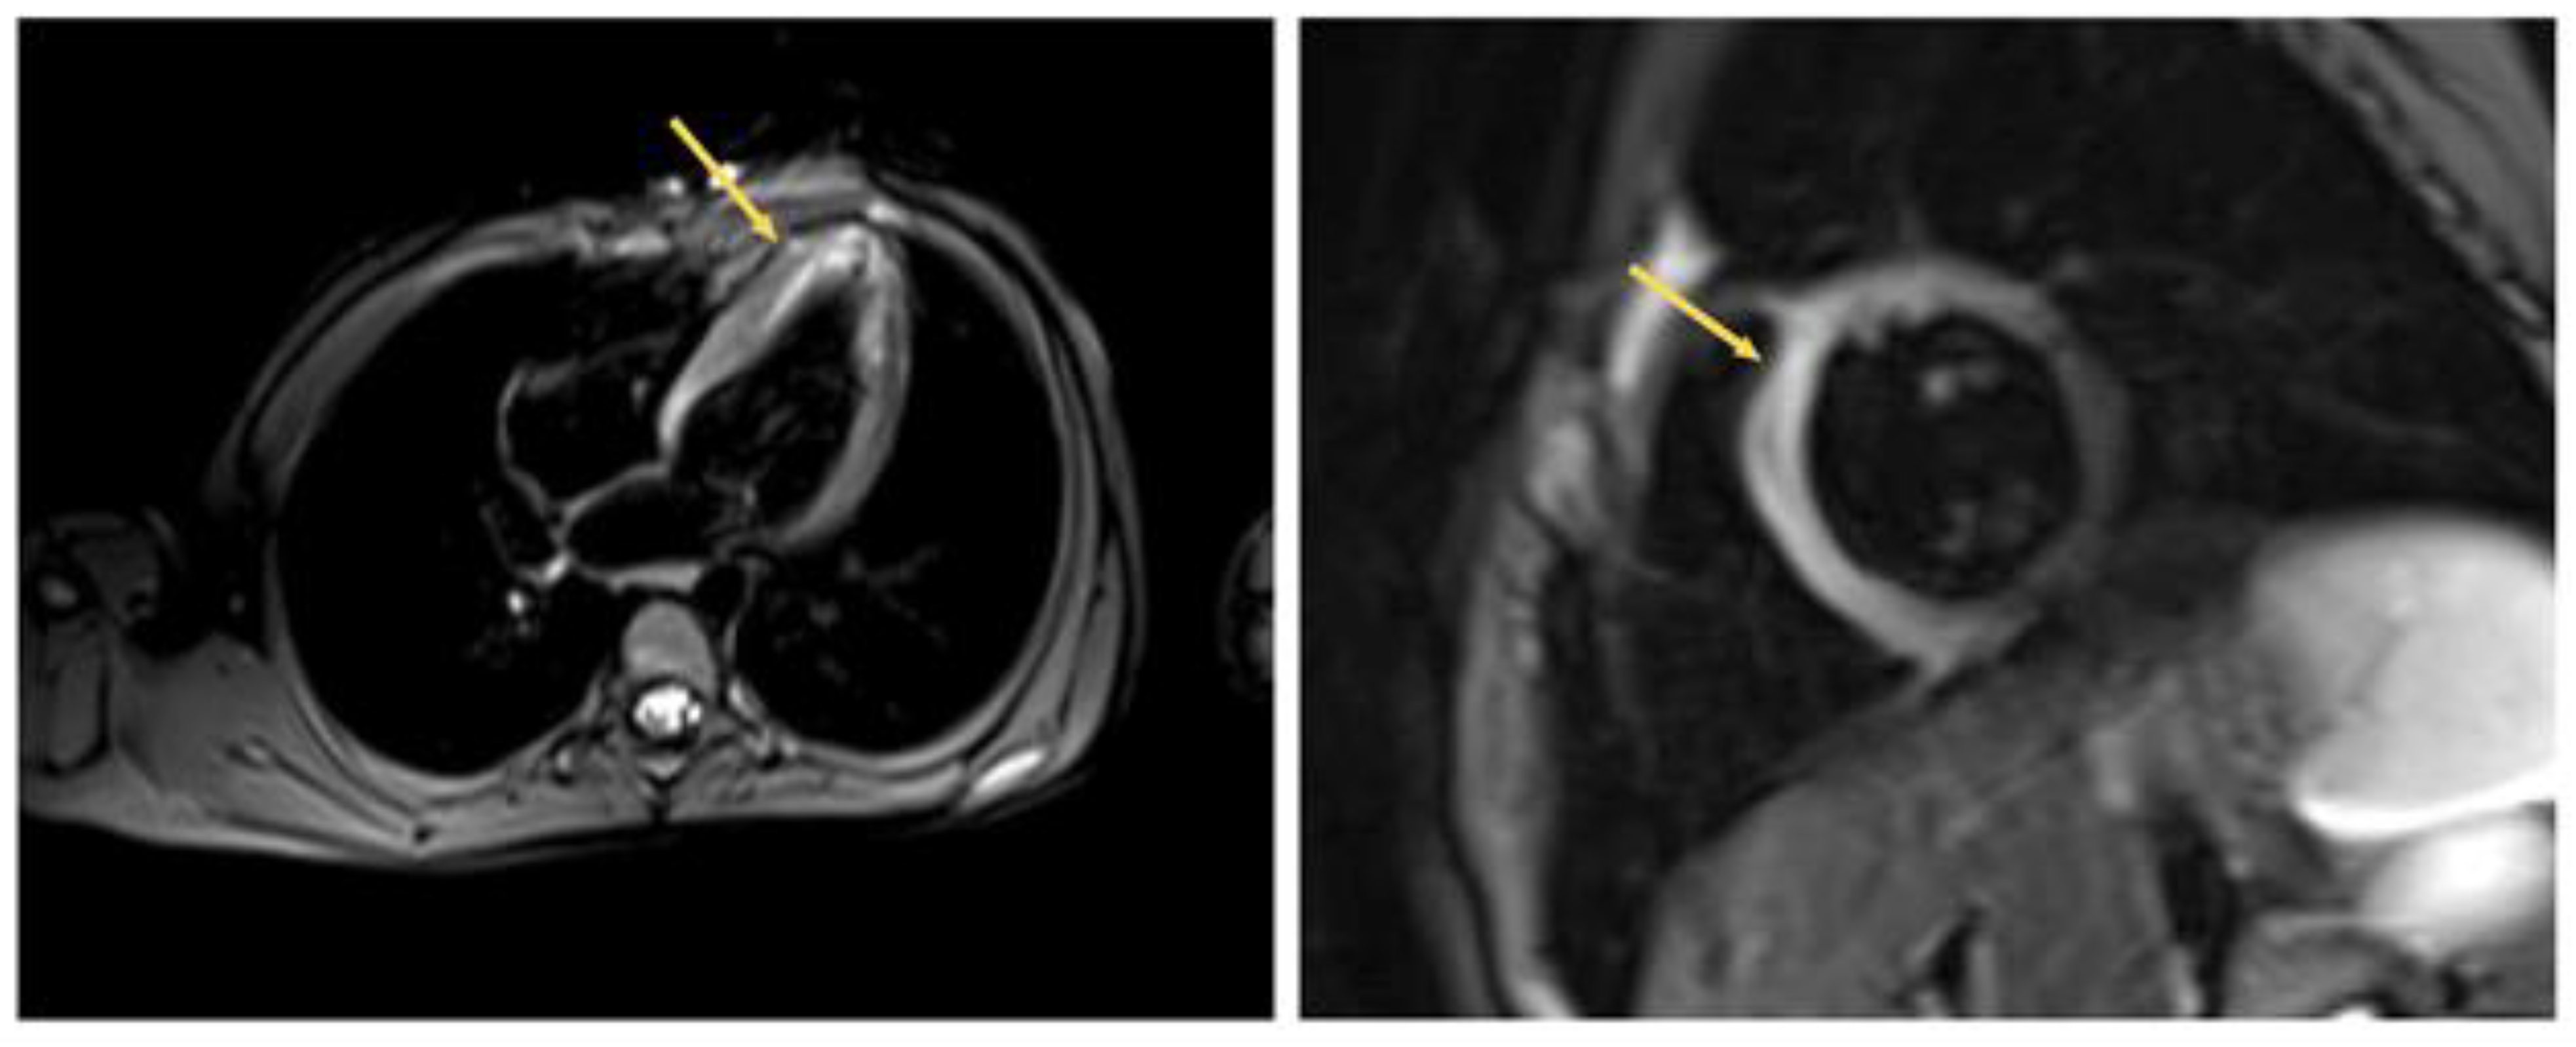

2. Case 1

2.1. Examination Data

2.2. Substantiation of Diagnosis

3. Case 2